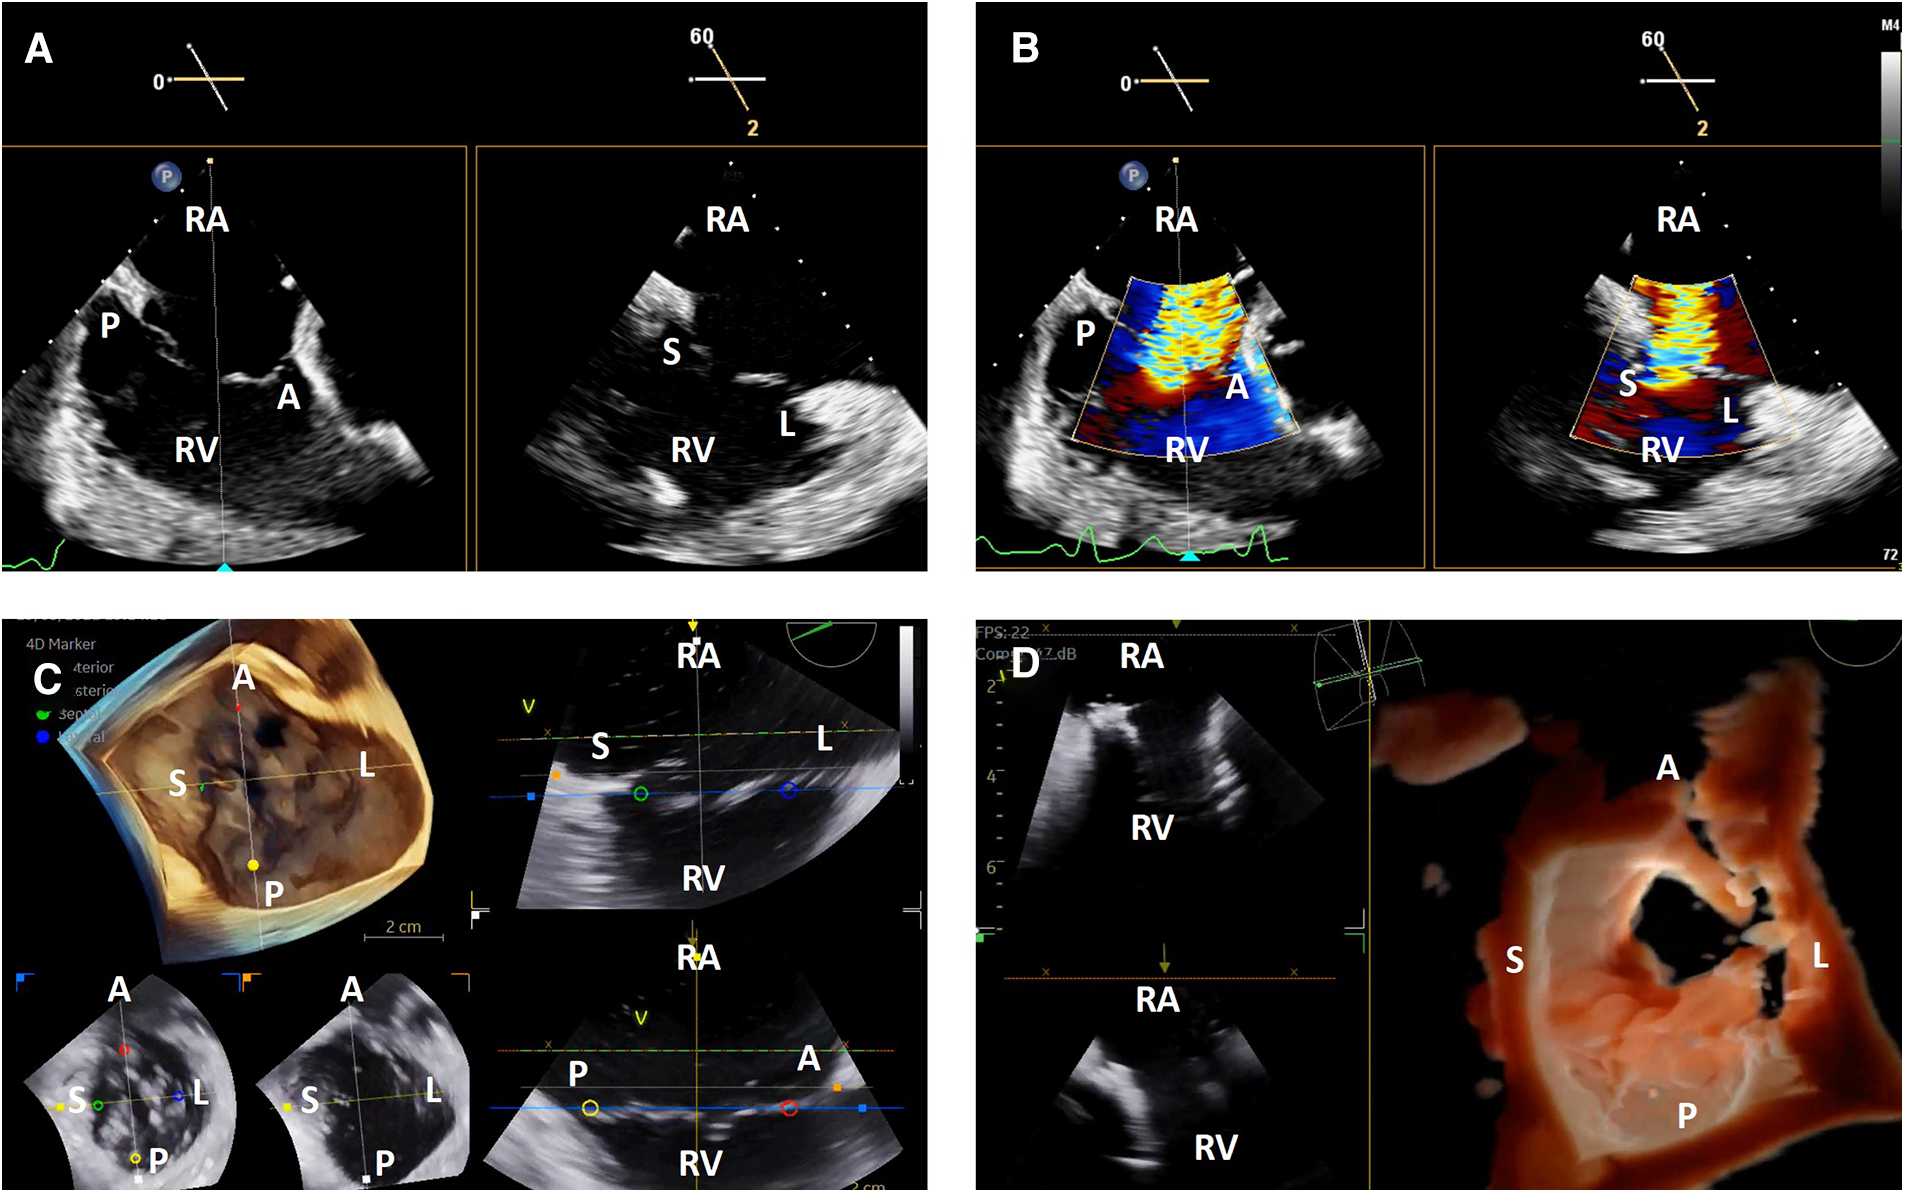

TEE image quality during transcatheter tricuspid interventions is variable due to the position of the tricuspid valve relative to the TEE probe. When the atria are dilated, the tricuspid valve may be in the far field for TEE. There may also be significant acoustic shadowing from intracardiac structures and prostheses. Lastly, cardiac chamber dilation often causes esophageal displacement relative to the atrioventricular valves, creating a “horizontal” appearance and further acoustic shadowing of the valve once delivery catheters are placed in the heart. Due to these factors, 3-dimensional ICE has significant advantages over TEE. The right atrial position of the probe places the tricuspid valve in the near field and avoids acoustic shadowing from left-sided structures and the crux of the heart (Figure 3).

Figure 3

3-dimensional intracardiac echocardiography for transcatheter tricuspid interventions. Biplane intracardiac echocardiographic evaluation of the tricuspid valve without (A) and with (B) color Doppler; (C) live 3-dimensional multi-planar reconstruction of the tricuspid valve with color-coded anatomic markers and two independently controlled short axis views on the bottom left (leaflet tip level on the left, annulus level on the right); (D) 3-dimensional en face view of a degenerated prosthetic tricuspid valve in diastole with two simultaneous 2-dimensional image plane reconstructions, obtained during a tricuspid valve-in-valve implantation. RA, right atrium; RV, right ventricle; A, anterior; P, posterior; S, septal; L, lateral.

The tricuspid valve is well-visualized using ICE without significant manipulation. Once the catheter is introduced into the right atrium from the inferior vena cava, the tricuspid valve is immediately visualized in the ICE “home view”. From this position, left or right flexion can be used to optimize angulation of the transducer face relative to the commissures to obtain the best biplane and 3-dimenional imaging, similar to what is described above for the mitral valve (6).

One of the critical TEE views used in transcatheter tricuspid interventions is the en face view where all leaflets are visualized in short axis (7). This is typically obtained from the shallow transgastric TEE window. 3-dimensional ICE catheters in the right atrium are not positioned to replicate this view with 2-dimensional imaging, and while live 3-dimensional imaging can provide this view, it does not have the same spatial and temporal resolution as TEE. As a result, the lack of this view may be a limitation for some transcatheter tricuspid interventions and current 3-dimensional ICE workflows often combine ICE with TEE imaging (Figure 3).